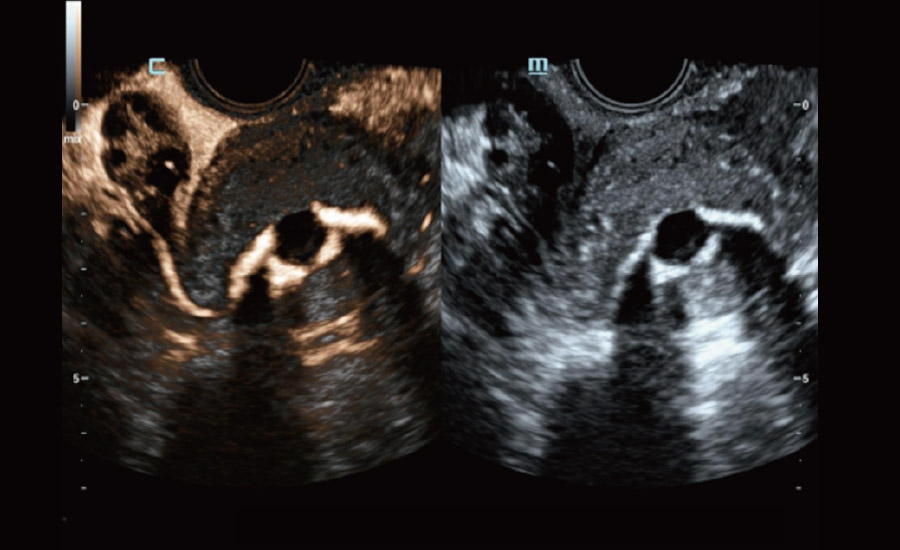

UMA (Ultra-Micro Angiography)

The innovative technology breaks the bottlenecks of traditional Doppler imaging. With ultra-high spatial resolution and flow sensitivity, it allows detecting super-subtle and super-slow flow perfusions, thereby extending the clinical application of qualitative and quantitative ultrasound evaluation in fetal brain, kidney, placenta, endometrium, ovary, etc.

UMA - fetus renal flow

UMA - uterine and endometrial flow